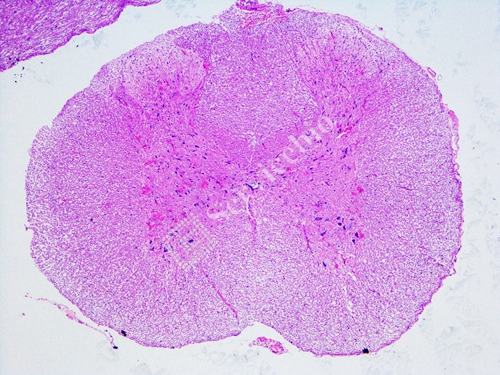

Rat (Spinal Cord) Histology and Morphology